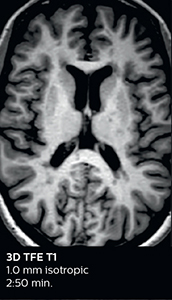

Improving scan time and/or spatial resolution

A two year follow-up scan of a CPA meningioma using both Ingenia 3.0T without CS and Ingenia Elition 3.0T with Compressed SENSE allows for a nice comparison to demonstrate the protocol improvements achieved on the Elition: 3D FLAIR has a shortened scan time, improved SNR and still the same spatial resolution. BrainView (3D T1 TSE) has improved spatial resolution and SNR with shortened scan time. For 3D T2 Drive the spatial resolution has been improved. 3D THRIVE used to have an interpolated 0.8 mm slice thickness, but true thickness at 1.6 mm, so that axial slices displayed a decent quality, but reformats were suboptimal. Compressed SENSE is used on Elition to improve spatial resolution and reduce the non-interpolated slice thickness to allow smoothly reformatted images. Total scan time (adding SmartBrain and an additional b2000 diffusion) was 13:19 on Ingenia, and is now reduced to 10:42 on Ingenia Elition.

Ingenia 3.0T (without Compressed SENSE)

3D FLAIR 1.0 x 1.0 x 1.0 mm* 4:24 min.

3D TSE T1w 1.0 x 1.0 x 1.2 mm* 2:40 min.

3D T2w Drive 0.8 x 0.8 x 1.0 mm* 3:05 min.

3D T1w THRIVE 0.8 x 0.8 x 1.6 mm* 1:30 min.

Ingenia Elition 3.0T with Compressed SENSE

3D FLAIR 1.0 x 1.0 x 1.0 mm* 2:50 min.

3D TSE T1w 1.0 x 1.0 x 1.0 mm* 2:10 min.

3D T2w Drive 0.7 x 0.7 x 0.7 mm* 2:52 min.

3D T1w THRIVE 0.7 x 0.7 x 0.8 mm* 1:30 min.

*true voxel size, without interpolation